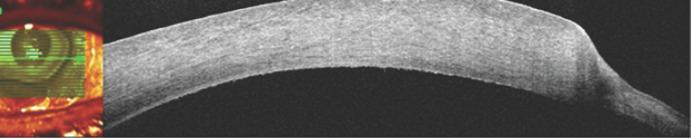

Granulomatosis with polyangiitis (GPA) is a granulomatous-necrotic systemic vasculitis with a lesion of predominantly the upper and lower respiratory tracts at the onset of the disease (vasculitis, accompanied by granulomatous inflammation), and subsequently renal (glomerulonephritis). In addition, GPA may manifest as inflammation of small arteries and veins. Despite many years of study of this disease, the etiology of GPA remains unknown. The present case is about a 47-year-old female, who had been suffering from necrotizing scleritis, corneal ulcer, and secondary glaucoma in both eyes for 3 months, and she was treated with anti-inflammatory and antimicrobial therapy that showed no effect; the patient's general condition became worse. In the second week of treatment, multiple abscess ruptures exposed the sclera. Sampling of the affected conjunctival tissue and positive HLA B8 haplotype and ANCA (PR3-ANCA) testings make it clear that GPA was the main reason of necrotizing scleritis with inflammation. The targeted treatment of the underlying disease allows to stabilize an inflammation of corneal and scleral lesions.

肉芽肿性多血管炎(GPA)是一种肉芽肿性坏死性系统性血管炎,疾病发作时主要累及上、下呼吸道(血管炎,伴有肉芽肿性炎症),随后累及肾脏(肾小球肾炎)。此外,GPA可表现为小动脉和静脉炎症。尽管对该疾病进行了多年研究,但其病因仍不明。本病例为一名47岁女性,双眼坏死性巩膜炎、角膜溃疡和继发性青光眼3个月,接受抗炎和抗菌治疗无效,病情恶化。治疗第二周,多处脓肿破裂暴露巩膜。对受累结膜组织取样以及HLA B8单倍型和抗中性粒细胞胞浆抗体(PR3-ANCA)检测呈阳性,明确GPA是坏死性巩膜炎伴炎症的主要原因。针对基础疾病的靶向治疗可稳定角膜和巩膜病变的炎症。